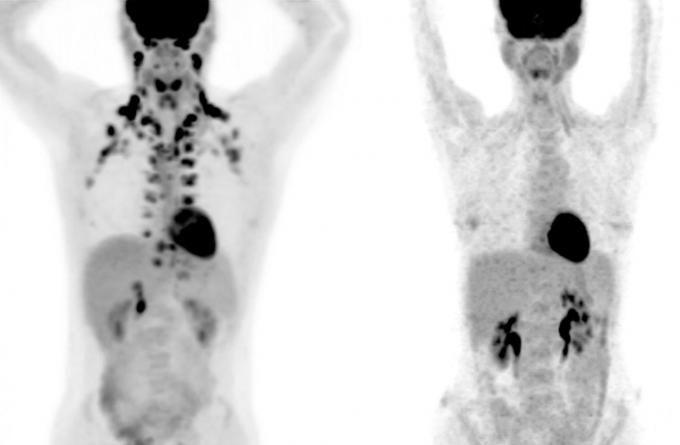

▲목과 경추에서 많은 양의 갈색지방이 관찰된 PET스캔(좌측). 우측 PET에선 갈색지방이 전혀 잡히지 않았다. (자료=연합뉴스)

갈색지방은 양전자 단층촬영(PET) 스캔을 해야 어느 부위에 있는지 알아낼 수 있다. PET는 비용이 많이 들고 방사선 노출에 따른 부담도 따른다. 그래서 연구팀은 가까운 거리에 있는 메모리얼 슬론 케터링(MSK) 암 센터의 과학자들과 공동 연구를 했다.

MSK에선 암 진단을 위해 많은 PET 검사가 이뤄지는데, 종양으로 오진하는 걸 막기 위해 PET에 잡힌 갈색지방을 따로 기록한다. 5만2000여 명의 피검자에게서 나온 13만여건의 PET 스캔을 분석한 결과, 거의 10%가 갈색지방을 갖고 있는 것으로 확인됐다.